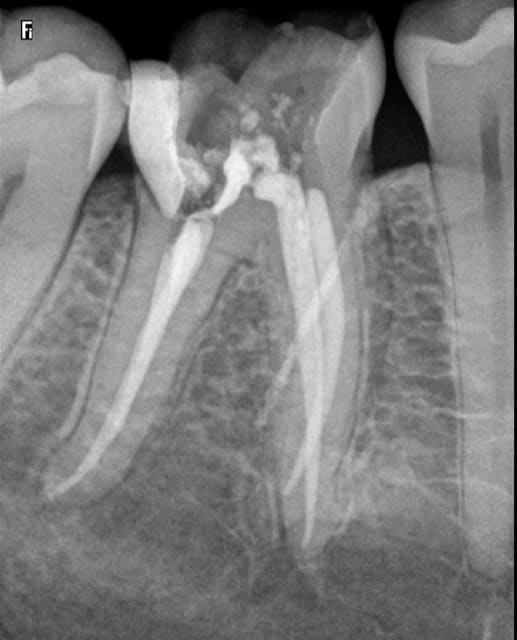

une fusée de gutta aussi bien cylindrique ça me parait bizarre.

Limite je te soupçonne de vouloir nous troller. N'y avait il pas une fistule en vestibulaire sur cette dent que tu aurais matérialisé?

Une trainée de pâte endo/morceau de gutta sur le capteur radio?

On dirait que l'image commençait déjà à apparaître sur la radio cone + pate non foulée.

percer une racine ca me semble difficile quand même. Mais c'est vrai que l'image ne m'évoque qu'une fuite de pâte dans le trajet de l'aiguille. serais tu juste tangent et a cote d'un canal secondaire?